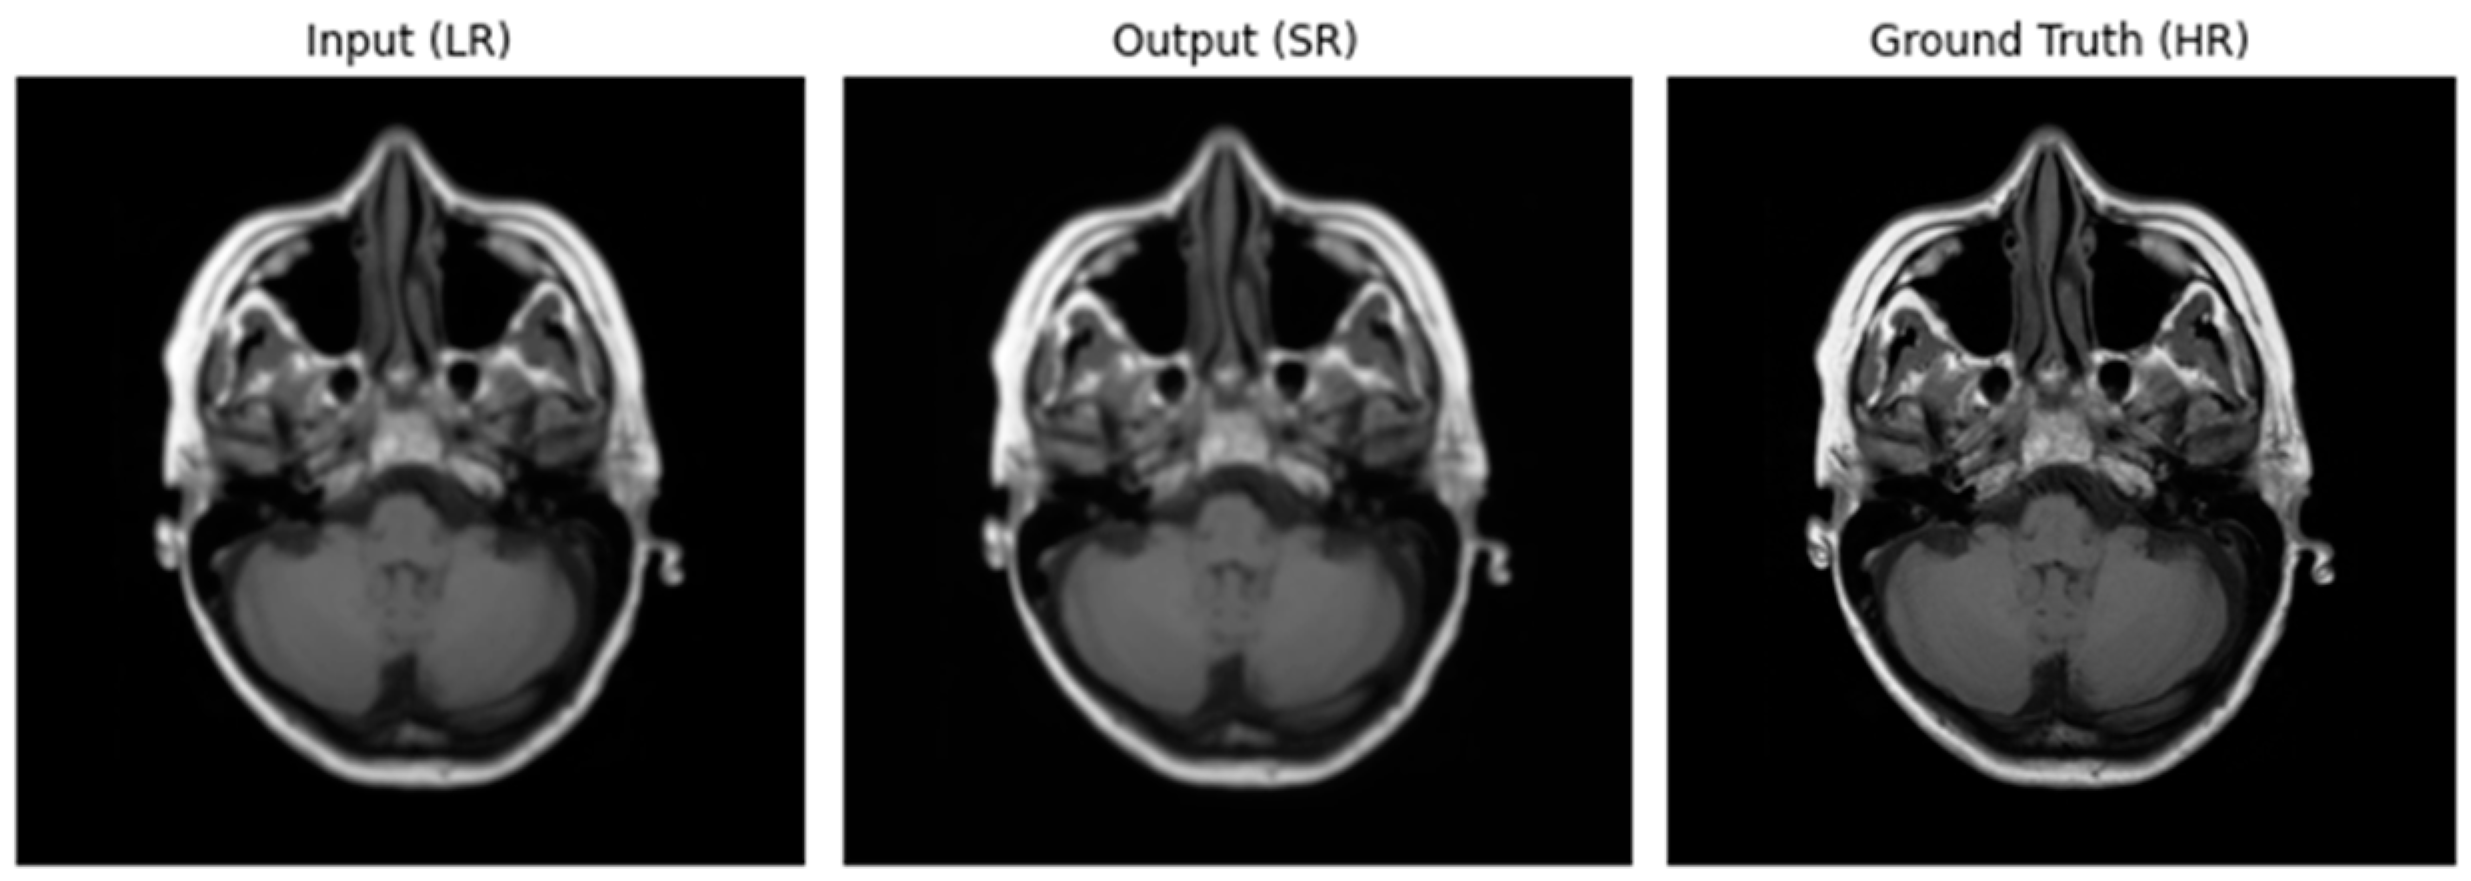

3.2. Performance of ADAM Optimizer and Use of Loss Functions Using Super Resolution Convolution Neural Network (SRCNN)

3.3. Performance of ADAM Optimizer and Use of Loss Functions Using Super Resolution Residual Network (SR ResNet)

3.4. Comparative Analysis Table of SRCNN and SR ResNet with ADAM Optimizer and Loss Functions